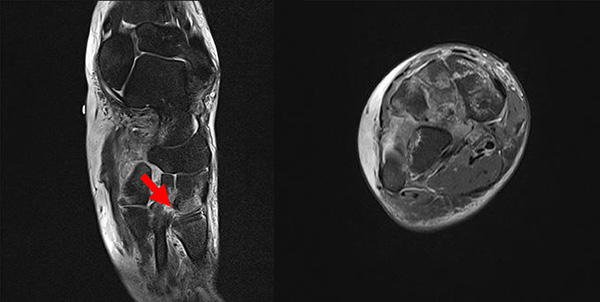

Das Lisfranc-Ligament selbst lässt sich am Besten im MRT beurteilen. Gelegentlich lässt sich im MRT ein Knochenmarksödem als einziges Zeichen einer nicht dislozierten Fraktur finden. Die MRT-Diagnostik ist allerdings eher unklaren interossären Erweiterungen bei persistierenden Schmerzen zur Suche nach isolierten Bandverletzungen vorbehalten 7511.

Zum Lesen der Bildbeschreibung und zur Vollansicht bitte das Bild anklicken.